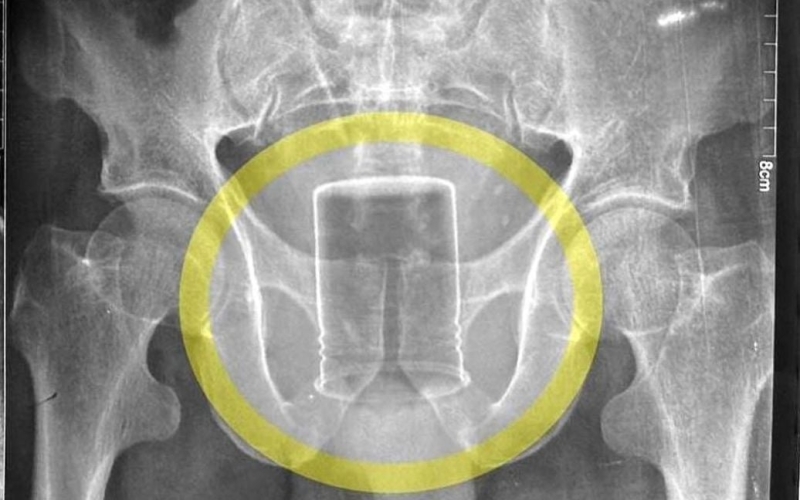

Чоловік, який запхав собі до ануса банку з інсектицидом, залишив її в прямій кишці на шість тижнів. Це сталося після того, як іншому чоловікові засунули в задній прохід 20-сантиметрову секс-іграшку.

Як повідомляє Need To Know, 56-річний фермер вставив чужорідний предмет за допомогою палиці, коли “випасав худобу на сусідньому полі”.

Пацієнт поквапився до лікарні, де йому сказали, що у нього розвинувся сепсис на пізній стадії. Медики також зазначили, що його психічний стан “задовільний”. Вони призначили внутрішньовенні крапельниці та антибіотики, і банку було успішно видалено без необхідності хірургічного втручання.